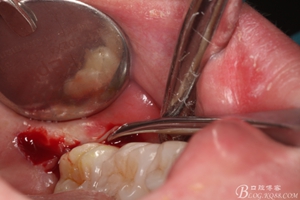

圖8. 翻瓣:建議翻小瓣

圖9.翻開瓣,可見38部分牙冠暴露